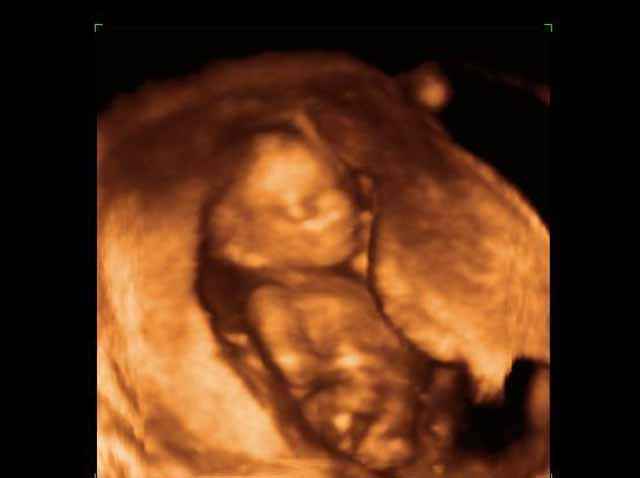

- تصرفات الجنين داخل الرحم

- صور لتصرفات الجنين داخل الرحم

صور لتصرفات الجنين داخل الرحم بجهاز الالتراساوند ثلاثي الأبعاد | الدكتور نجيب ليوس